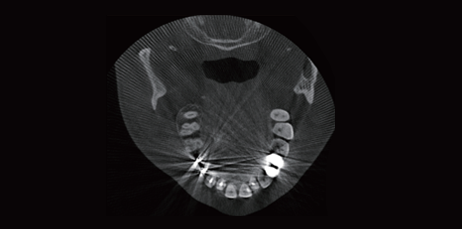

Reducción de Artefactos Metálicos

With the new T-MAR reduction module for metal artifact removal, the system corrects metal artifacts intelligently. It avoids overmodification and saves the original clinical data.

Implant Simulation

It can evaluate the bone quality and bone quantity of the implant area, automatically outline the neural tube. Clarifying the relationship between the implant position and the adjacent anatomical structure to accurately select the implant position, the optimal length and diameter of the implant. It can improve the success rate, and avoid possible nerve or blood vessel damage.